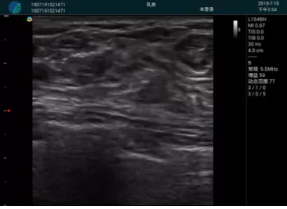

清晰顯示孕囊,通過軟件包計(jì)算孕齡7w+6d

M20實(shí)時引導(dǎo),術(shù)中清晰顯示孕囊被破壞和抽吸針的過程,清晰顯示吸引針

抽吸結(jié)束后縱切子宮,孕囊已被完全抽吸,未見明顯殘留

橫切子宮,發(fā)現(xiàn)右側(cè)宮腔靠近宮角處有少許脫模樣殘留

M20引導(dǎo)下,抽吸針找到右側(cè)宮角處再次清掃

二次抽吸后再次進(jìn)行超聲檢查,宮腔未見殘留,宮腔線清晰顯示